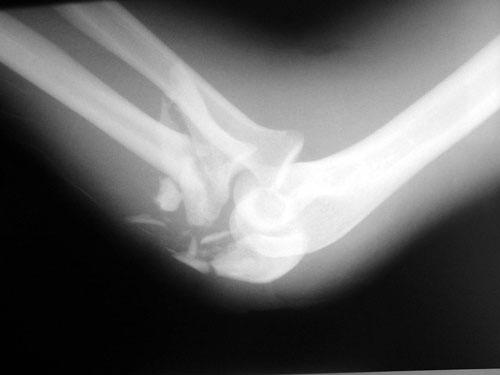

AC is a 25 year old male who was assaulted with a baseball bat. He sustained a shattered proximal ulna fracture with elbow dislocation. Surgery required application of a plate and screws, as well as pinning and cerclage wiring. He worked diligently in therapy to regain the excellent range of motion in his elbow as demonstrated in the photo with me.